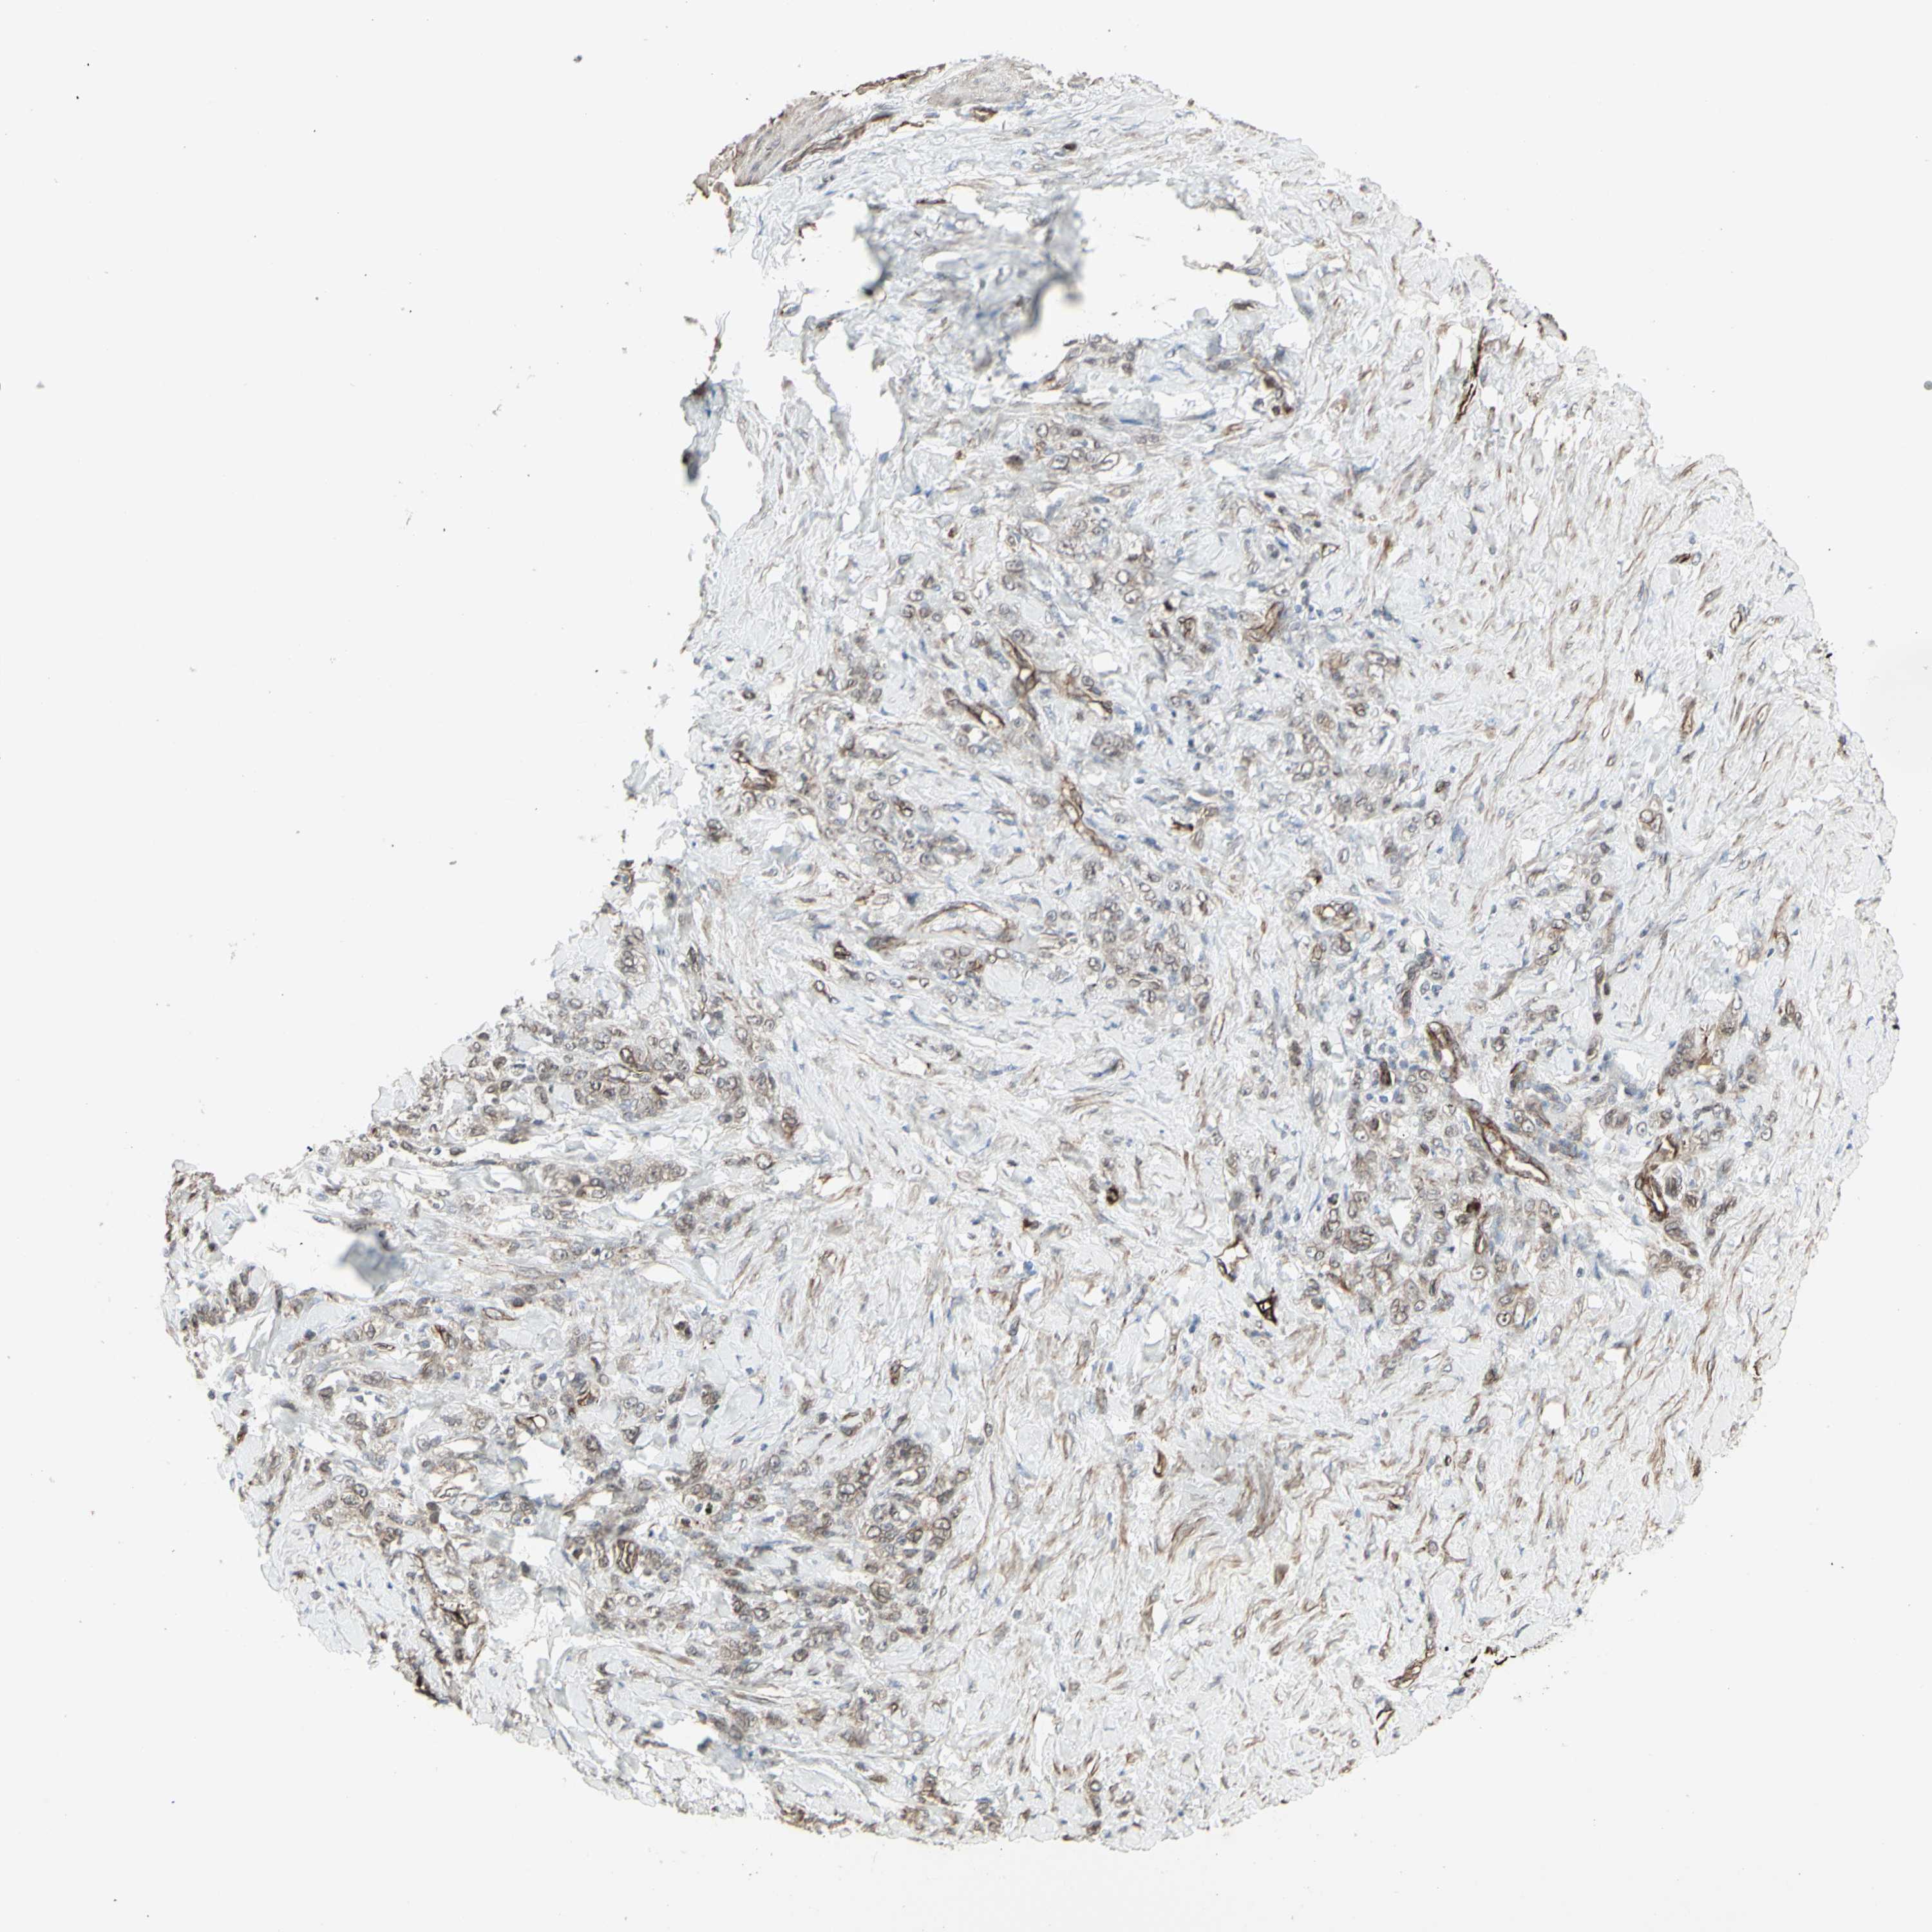

STOMACH CANCER - Protein expressioni

A mouse-over function shows sample information and annotation data. Click on an image to view it in a full screen mode. Samples can be filtered based on level of antibody staining by selecting one or several of the following categories: high, medium, low and not detected. The assay and annotation is described here.

Antibody stainingi

Antibody staining in the annotated cell types in the current human tissue is reported as not detected, low, medium, or high, based on conventional immunohistochemistry profiling in selected tissues. This score is based on the combination of the staining intensity and fraction of stained cells.

Each image is clickable and will lead to virtual microscopy that enables deeper exploration of all samples and also displays staining intensity scores, fraction scores and subcellular localization as well as patient and tissue information for each sample.

Antibody HPA010570

Staining

High

Medium

Low

Not detected

Intensity

Strong

Moderate

Weak

Negative

Quantity

>75%

75%-25%

<25%

None

Location

Nuclear

Cytoplasmic/membranous

Cytoplasmic/membranous,nuclear

Adenocarcinoma, NOS

Adenocarcinoma, High grade